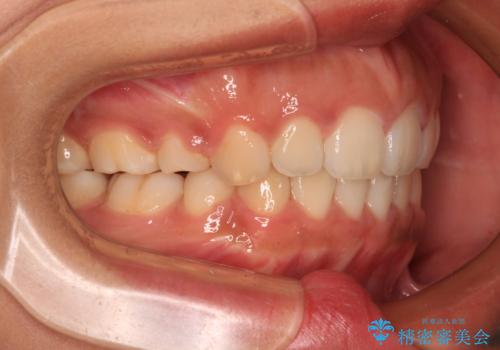

舌の突出癖により上下前歯は非接触であり、非常に前方に飛び出している状態でした。

舌のトレーニングをしっかりと行っていただき、口の閉じやすい歯並びに仕上げることができました。

- 出っ歯と口の閉じにくさ、デコボコを気にして来院された患者様です。

口元の突出感を改善するため、上下左右第一小臼歯4本の抜歯を行い、ワイヤー装置による矯正治療を行うこととしました。